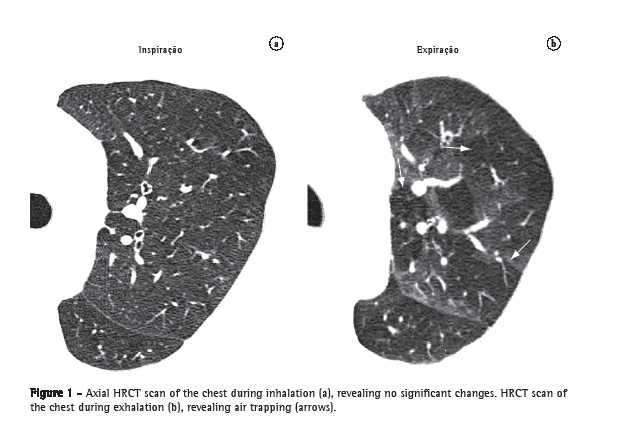

Air trapping (aprisionamento aéreo)

Air trapping is the retention of excess gas (air) in part of or all of the lung (especially upon exhalation), resulting from partial or total airway obstruction or secondary to focal abnormalities of lung compliance. It is recognized during the expiratory phase as reduced attenuation of the lung parenchyma, especially apparent as lower-than-usual density (Figure 1) and absence of volume reduction.(8-10)

See also Mosaic attenuation/perfusion pattern.